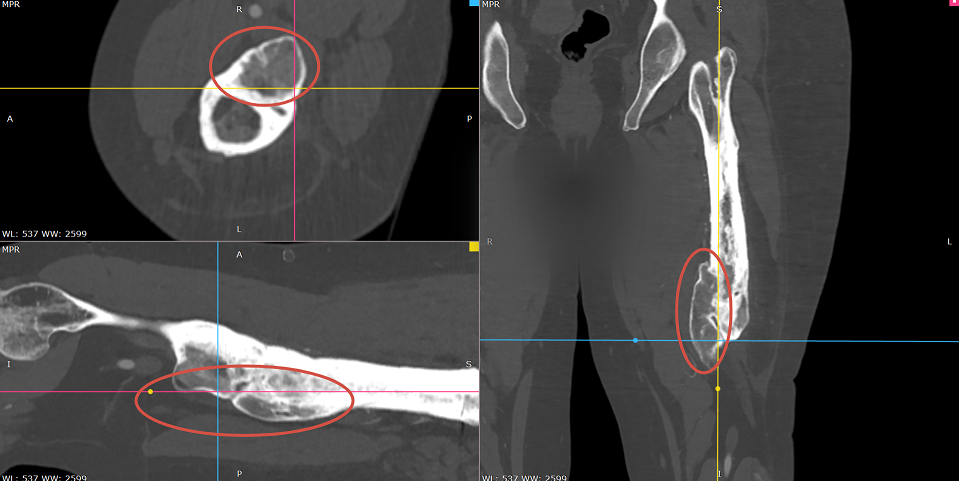

Наталья прошла через многократные хирургические вмешательства (остеосинтез, костная пластика и другие), однако спустя годы лечение не завершилось — вследствие ряда факторов у пациентки сохранялись деформации конечностей. В левой бедренной кости образовался экзостоз — большая костная мозоль, по диаметру сравнимая с ещё одной бедренной костью.

«Проблема заключалась в том, что перелом бедренной кости с левой стороны сросся в положении умеренной деформации, и в средней трети диафиза наросла костная мозоль критичных размеров (40×70×30 мм) со сдавлением ветви бедренной артерии и бедренного нерва. То есть сосудисто-нервный пучок был спаян с этой мозолью, что вызывало выраженные болевые ощущения.

На операцию мы пошли вместе с сосудистым хирургом: выделили сосудисто-нервный пучок, аккуратно отвели в сторону и удалили примерно 90% экзостоза: не полностью, чтобы не повредить и так деформированную бедренную кость», — объясняет к.м.н., врач-травматолог-ортопед Сергей Корочкин.